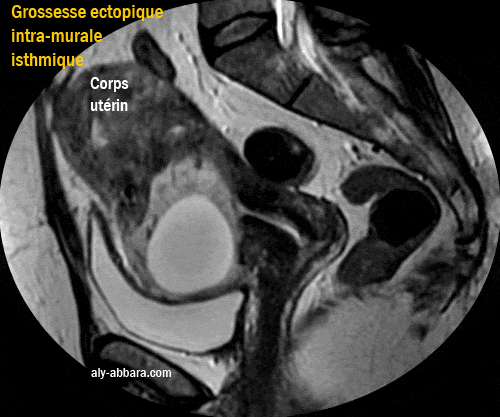

• Images d'IRM montrant une grossesse ectopique évolutive de 10,5 SA, localisée dans la paroi antérieure de la région isthmique de l'utérus ; il s'agit d'une localisation rare de la grossesse ectopique (grossesse extra-utérine intramurale isthmique) pouvant être expliquée par la présence d'un diverticule (ou une béance) dans l'ancienne cicatrice d'une césarienne permettant la nidation de la grossesse dans cette zone de la paroi utérine.

Ce sac gestationnel n'est pas localisé dans la cavité utérine, car il s'est développé dans la paroi antérieure de la région isthmique de l'utérus, avec une évolution, en particulier antérieure, vers la paroi postérieure de la vessie, mais heureusement, il reste séparé d'elle par une fine couche myométriale qui ne dépasse pas les 2 mm d'épaisseur.

• Ces données échographiques ont été confirmées par l'IRM qui permet de mettre en évidence les rapports anatomiques de cette grossesse avec les organes avoisinants et qui prouve l'intégrité de la paroi vésicale postérieure.